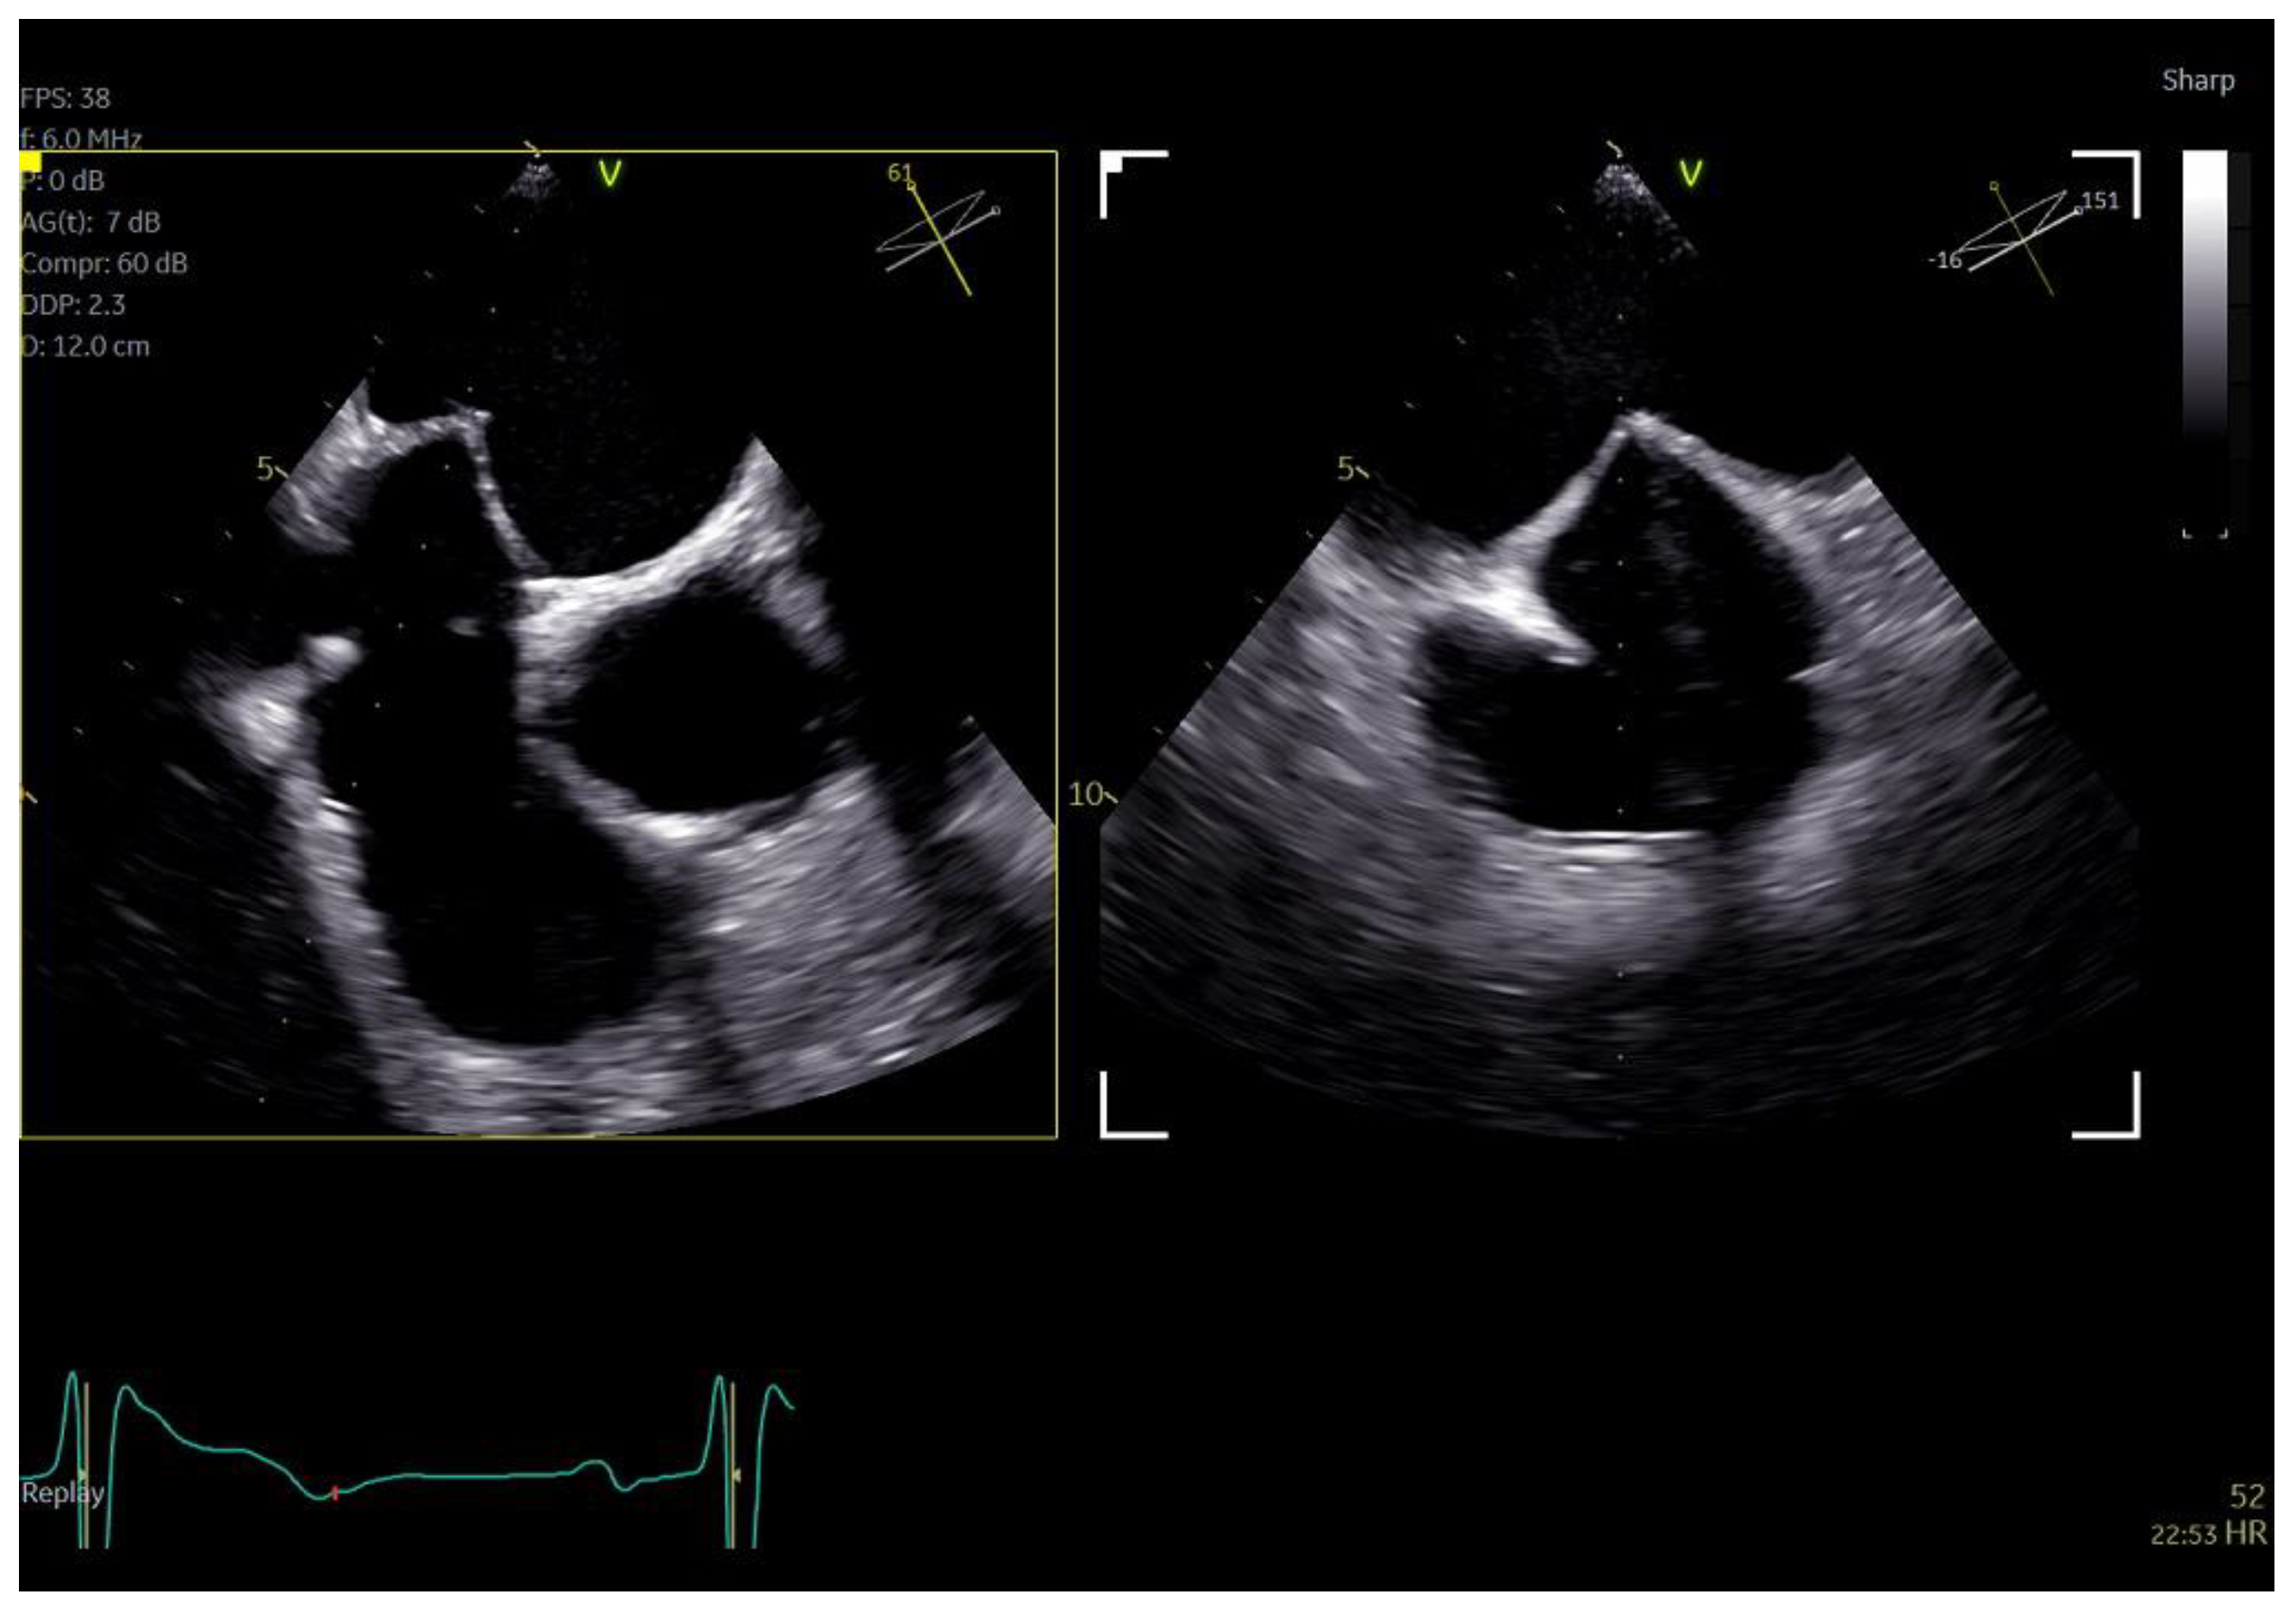

Figure 5.

Biplane images of tending of the atrial septum during trans−septal puncture for atrial fibrillation cryo−ablation.

Figure 6.

Azimuth level (top left), elevation level (bottom left), and 3D volume-rendered image (right) of an SL0 catheter for the guidance of cryo-ablation procedure.

The imaging capabilities of the 4D mini-TEE probe were consistently excellent across all procedures (Figure 5, Figure 6, Figure 7, Figure 8 and Figure 9). Trans-septal puncture in ablation cases was facilitated by biplane imaging (Figure 5), demonstrating a nice tending of the septum. For the guidance of wires to the pulmonary veins, both 2D and 4D volume-rendered images were utilized (Figure 5 and Figure 6), expediting the procedure. The TEE probe was removed after the insertion of the cryo-ablation catheter into the LA.